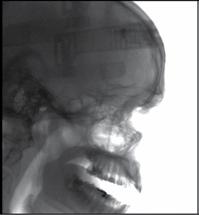

Nell’ambito della radiologia 3D ortopedica, il centro diagnostico utilizza il nuovissimo macchinario NewTom 5G XL, in grado di individuare con la massima precisione la presenza di fratture o lussazioni delle articolazioni, controllare la corretta guarigione di una frattura, valutare una lesione o una ferita causata da infezione, artrite o crescita anormale dell’osso.

Il tutto mediante una semplice e veloce scansione, grazie alla quale si otterranno diverse immagini in 3D ad altissima risoluzione e, per ottenere immagini ancora più nitide mediante un bassissimo dosaggio di radiazioni, gli esperti si avvalgono dell’innovazione racchiusa nella tecnologia Cone Beam.

Se con la radiologia tradizionale era necessario eseguire scansioni multiple, la novità introdotta dal macchinario NewTom 5G XL risiede nella capacità di fornire immagini ad alta risoluzione in un’unica scansione, mostrando nitidamente i dettagli delle articolazioni degli arti superiori e inferiori. Inoltre, a differenza della tecnologia 2D, la radiologia 3D ortopedica permette di individuare immediatamente alcune patologie come quella del metatarso, la quale richiede un allineamento visivo dedicato o una diagnosi delle micro fratture ossee.